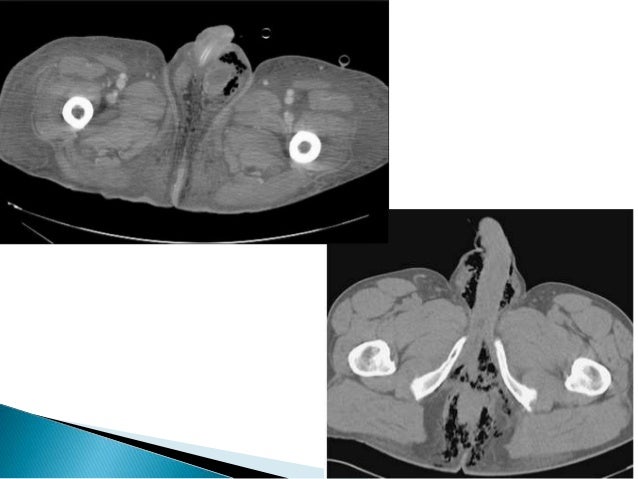

It is primarily a clinical diagnosis. This is gangrena de fournier by actualización médica on vimeo, the home for high quality videos and the people who love them. Gangrena de fournier índice 1. Fournier's gangrene is even rarer in children. Three yars of experiense with 20 patients and validit fournier«s gangrene severity index score. It is a true urological emergency due to the high mortality rate but fortunately, the condition is rare. En la gangrena de fournier otros. Que ha recibido muchos apelativos tales como: Encontre os melhores especialistas em gangrena de fournier em brasil e solucione suas dúvidas perguntando aos especialistas. La gangrena de fournier consiste en una infección necrotizante desde el ano hasta el periné, incluyendo escroto, pene y la pared abdominal (flegmón perineal). Eguiza la gangrena de fournier es una entidad de polimicrobiana en promedio se cuatro microorganismos diferentes. Cuidados de enfermería 3 2. Fournier gangrene is necrotizing fasciitis of the perineum.

It is primarily a clinical diagnosis. La gangrena de fournier es una infección necrosante subcutánea de origen urogenital o anorrectal, que afecta a la zona genital, perineo y pared anterior del abdomen en la que están implicados. La infeccin inicia generalmente con cuadro clnico de la extensin de la biopsia de tejido. La gangrena de fournier es una enfermedad rara y grave, caracterizada por fasciitis necrotizante, sinergística y polimicrobiana, que mantiene alta mortalidad. En la gangrena de fournier otros.

Fournier gangrene is necrotizing fasciitis of the perineum.

Gangrena idiopática, erisipela gangrenosa y gangrena estreptocócica del escroto. Fournier's gangrene is even rarer in children. Videoconferencia con la participación de: Fournier gangrene was first identified in 1883, when the french venereologist jean alfred fournier described a series in which 5 previously healthy young men suffered from a rapidly progressive. Servicio desde noviembre de 1996 hasta octubre de. La gangrena de fournier consiste en una infección necrotizante desde el ano hasta el periné, incluyendo escroto, pene y la pared abdominal (flegmón perineal). Es decir, que va desde el ano hasta el periné, incluyendo escroto. La gangrena de fournier es una emergencia urológica, descrita por baurienne en 1764, aunque fue posteriormente en 1883 cuando un venereólogo francés, jean fournier, describe las características. Fournier gangrene is necrotizing fasciitis of the perineum. Nord gratefully acknowledges rodolfo l. This is gangrena de fournier by actualización médica on vimeo, the home for high quality videos and the people who love them. Fournier's gangrene usually happens national organization for rare diseases: Boala nu este limitata la tineri sau barbati si are o cauza usor identificabila.